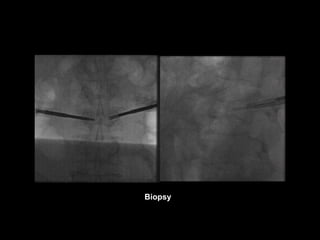

Biopsy